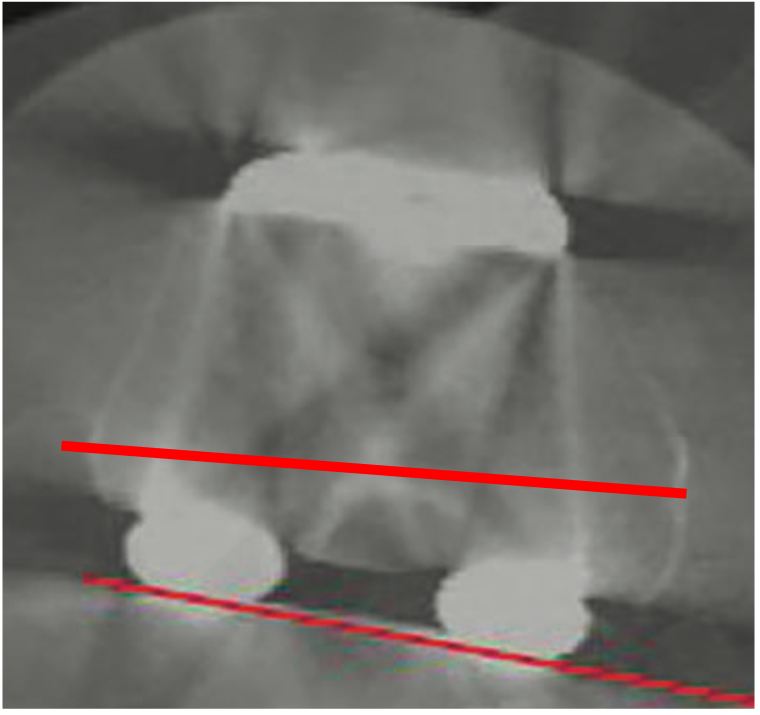

A bilateral CT scan is essential for obtaining official confirmation of rotational problems with the femoral and/or tibial components. In TKA patients with PFI the relevant measurement is the rotational alignment of the components relative to the landmarks of the knee. Malpositioning of the components must be measured by the posterior condylar angle for the femur (posterior condylar line to epicondylar axis) and anterior tibia tubercle angle for the tibia (AP line of tibia surface to TTA – Tibia tubercle to PCL line). The combined internal rotation of the tibia and femur component is directly correlated to the degree of patellofemoral instability (1–4° combined component rotation = lateral tracking and tilting; 4–8° = subluxation; >8° = early patellar dislocation with risk of loosening).[11]

These patients have total or partial lateral dislocation of the patella (Fig. 1). The cause is rotational malalignment of the femur and/or tibia implant (Fig. 2) or severe torsional limb malalignment with increased femur anteversion or excessive tibia internal rotation or both.